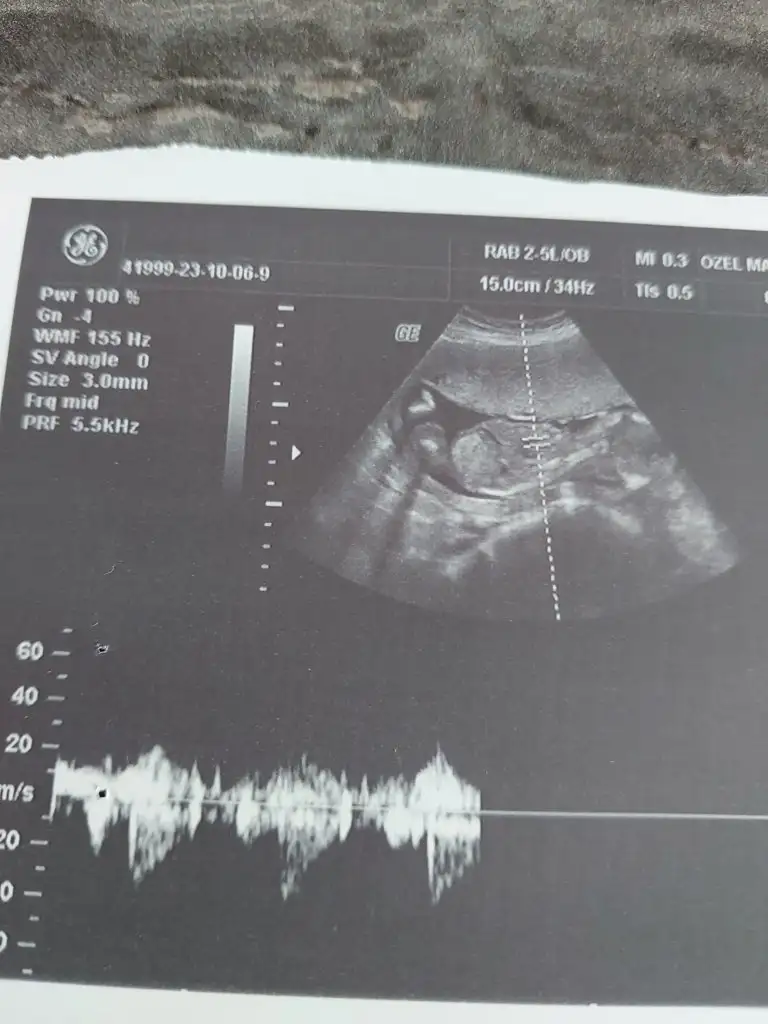

Arkadaşlar bana da önce 12+5 de kız dendi. 17 haftamda erkek dedi doktorum. Yanılabilir mi ? Sizde bir bakabilir misiniz? Hep kız hissediyorum :)12 ve 17 haftalara ait.